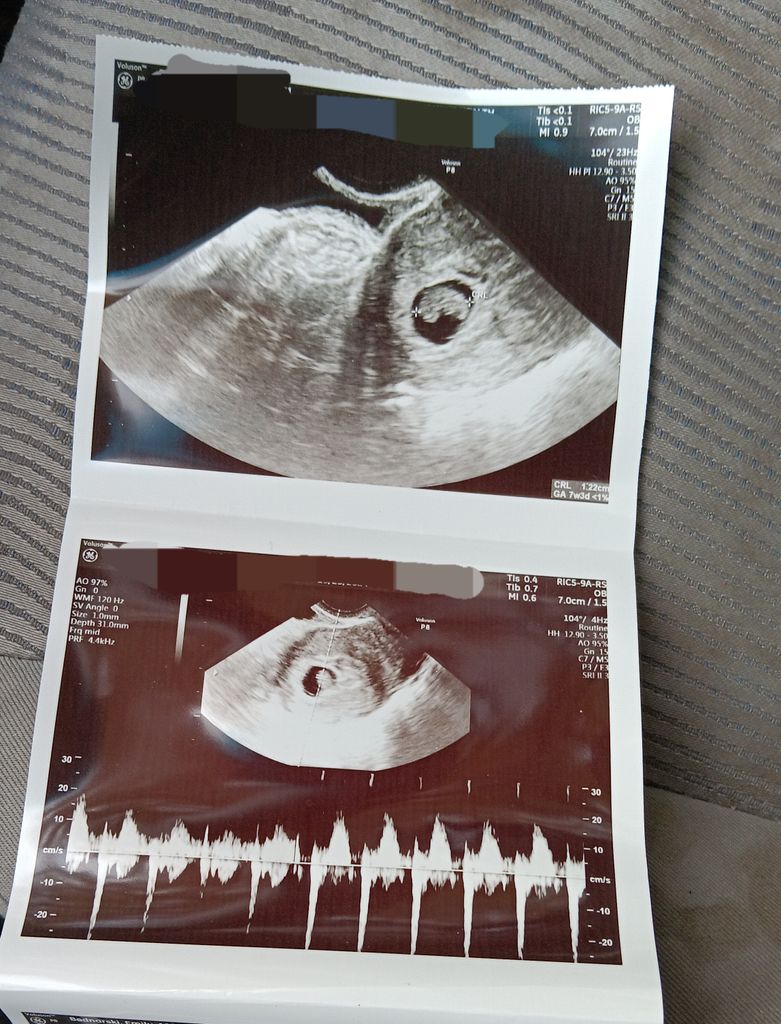

From community.whattoexpect.com

Advice from me, an ultrasound technologist June 2025 Babies Forums Can A Blood Clot Look Like A Miscarriage Some women may experience light bleeding or spotting during a normal. Spotting or bleeding during pregnancy doesn't necessarily mean you are having a miscarriage, but if you. It’s also common to have vaginal bleeding and to pass large blood clots up to the size of a lemon. Miscarriages can look and feel like a period, although they can also feel. Can A Blood Clot Look Like A Miscarriage.